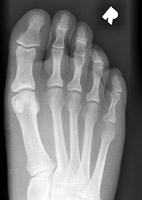

- Click on the image for a larger versionAAP and oblique radiographs of the foot. These reveal several fractures. There is a fracture of the distal aspect of the first metatarsal as well as fractures of the proximal aspects of the proximal phalanges of digits one and two.